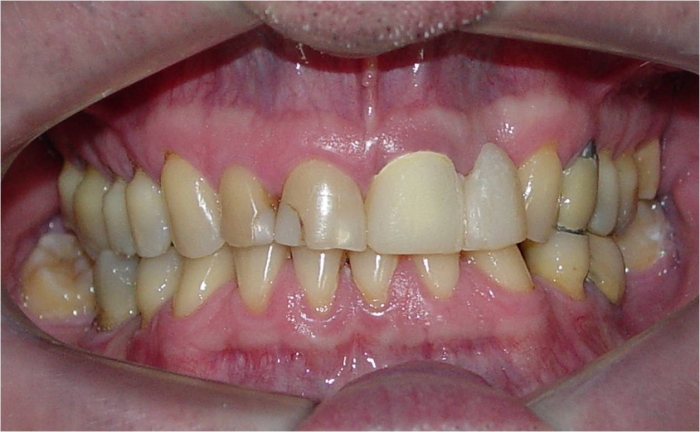

Imagens iniciais, mostrando ausência do elemento 22

Imagem inicial